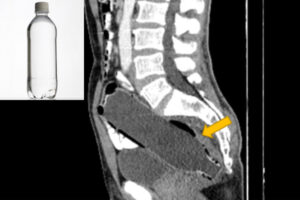

2022 07.17 便秘で来院した患者、CTを撮るとお尻の中にペットボトルが 国際ニュースまとめ 来院したイラン人男性の直腸から、長さ約19.3cmのペットボトルを取り出したという特異な事例が、医学専門誌「Clinical Case Reports Journal」に報告され、海外メディアに取り上げられている。 Source: Switch News もっと記事を見ていきませんか? 「幼児教育無償化に所得制限を」とは発言せず。反対の声相次いだ参院予算委での意見、中室牧子・慶大教授に聞いた。 Clinical trials for Ivermectin being eyed on Nov. 15: DOST タイ型変異株?イギリスで109人から「C.36.3」を検出 学校で銃乱射に備える訓練を行うアメリカ。子どもたちに及ぼす影響とは? Filipino Omicron case from Japan had one close contact who tested COVID-19 negative: DOH Philippines reports third Omicron case Tweet Share Hatena Pocket Post navigation 前の記事 次の記事 関連記事 コストコがトランプ政権提訴 なぜ 台湾当局「中国軍が海峡で模擬攻撃」 外国艦船を追跡… 2026年 タイ祝日・休日カレンダー 朝日新聞社・石合編集委員に韓国のメディア賞 朝鮮通… 本当に“日本版トラスショック”は生じないのか 獲物を狙うサメや人の顔の形をした火山噴火――国際航… タイ、数十年続いた午後の酒販売禁止を一時解除 J.Y.Parkが沖縄に家族旅行→娘2人との動画も… 【Wミリオン】両学長『お金の大学』は、なぜ&…